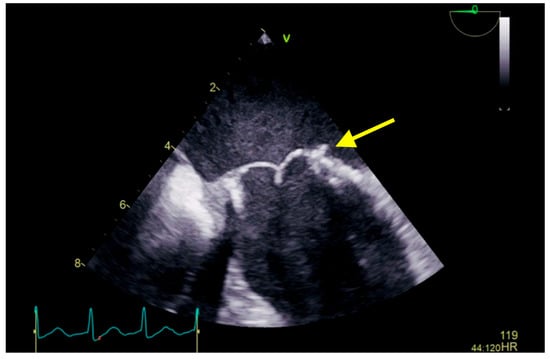

:1. Case Presentation